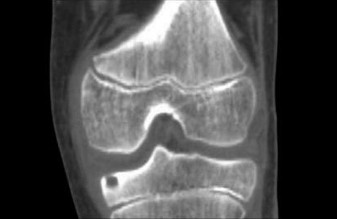

Ankle Arthritis Case: Easing Painful Plantar Flexion Hindfoot

A 48-year-old female presents to your office with worsening right ankle pain. Twenty years ago she sustained …